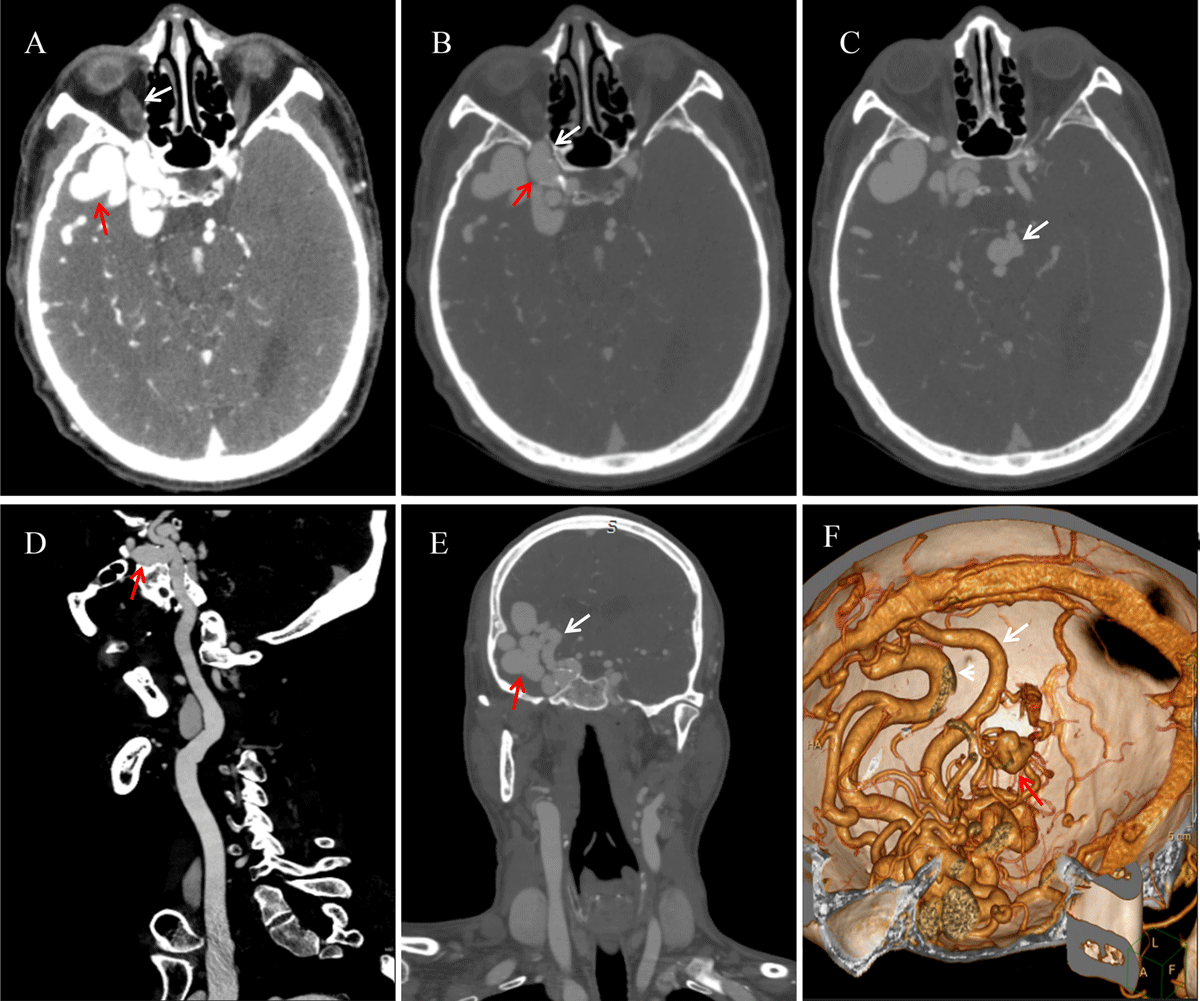

A 57-year-old man was rushed to the emergency room with intermittent convulsions. The patient had a five-year history of hypertension and a single seizure one year earlier. Axial computed tomography angiography (CTA) image (Figure 1A) showed a vascular mass (red arrow) and thickened, swollen inferior ophthalmic vein (white arrow). The bone window axial CTA image (Figure 1B) demonstrated a right internal cavernous sinus aneurysm locally protruding into the optic canal (red arrow) and optic canal enlargement compared to the contralateral side (white arrow). A basilar artery aneurysm was present (white arrow in Figure 1C). Multiplanar reformation sagittal image (Figure 1D) shows saccular aneurysm (red arrow) approximately 2.4 cm × 1.3 cm in size with a narrow neck originating from the cavernous segment of the right internal carotid artery. The bone window coronal CTA image (Figure 1E) demonstrates the feeding artery (white arrow) and the malformed vascular mass (red arrow), while the volume rendering (Figure 1F) illustrates the draining vein (white arrow) and the basilar artery aneurysm (red arrow).

Figure 1

CTA presentation of intracranial arteriovenous malformation combined with multiple aneurysms.